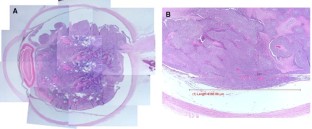

Fig. 1

Fig. 2